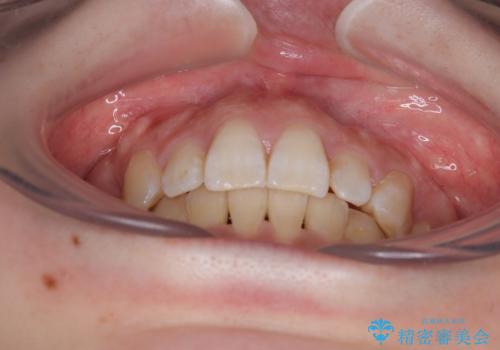

第二小臼歯抜歯としたため、治療期間は長くなりましたが、満足のいく仕上がりとなりました。

非抜歯矯正にて治療を行うと、仕上がりで口元が突出する可能性があったため、小臼歯抜歯での矯正治療を行うこととしました。

上顎は左右の第一小臼歯2本を、下顎は左右の第二小臼歯2本を抜歯して、口元が突出しないようにしながら、奥歯の咬み合わせを改善していく治療計画としました。

目立たない装置が希望であったため、上顎が裏側装置である、ハーフリンガル装置を選択されました。